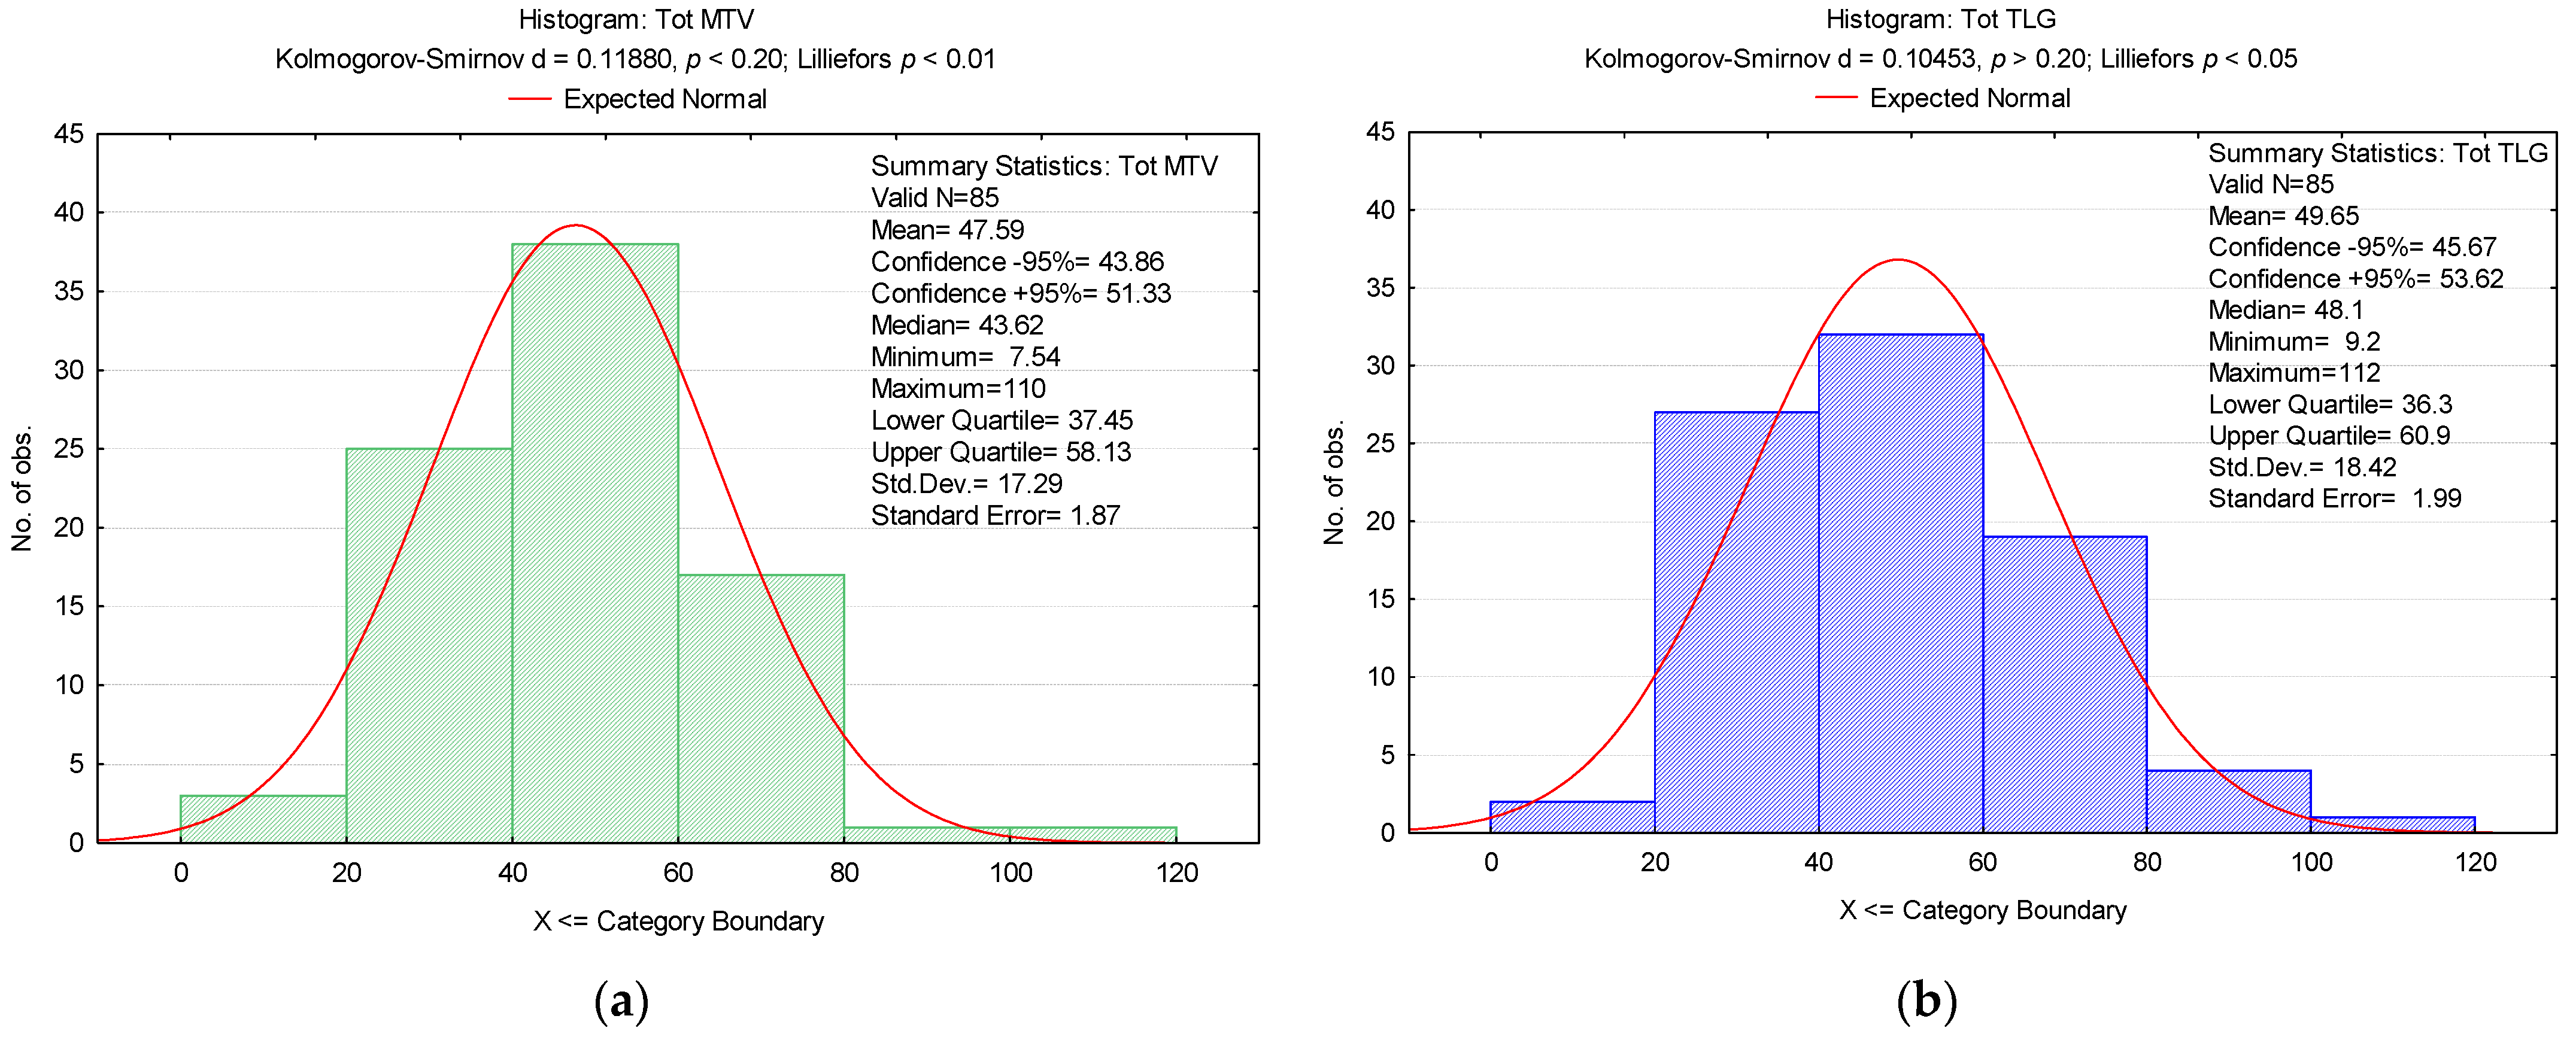

3. Results